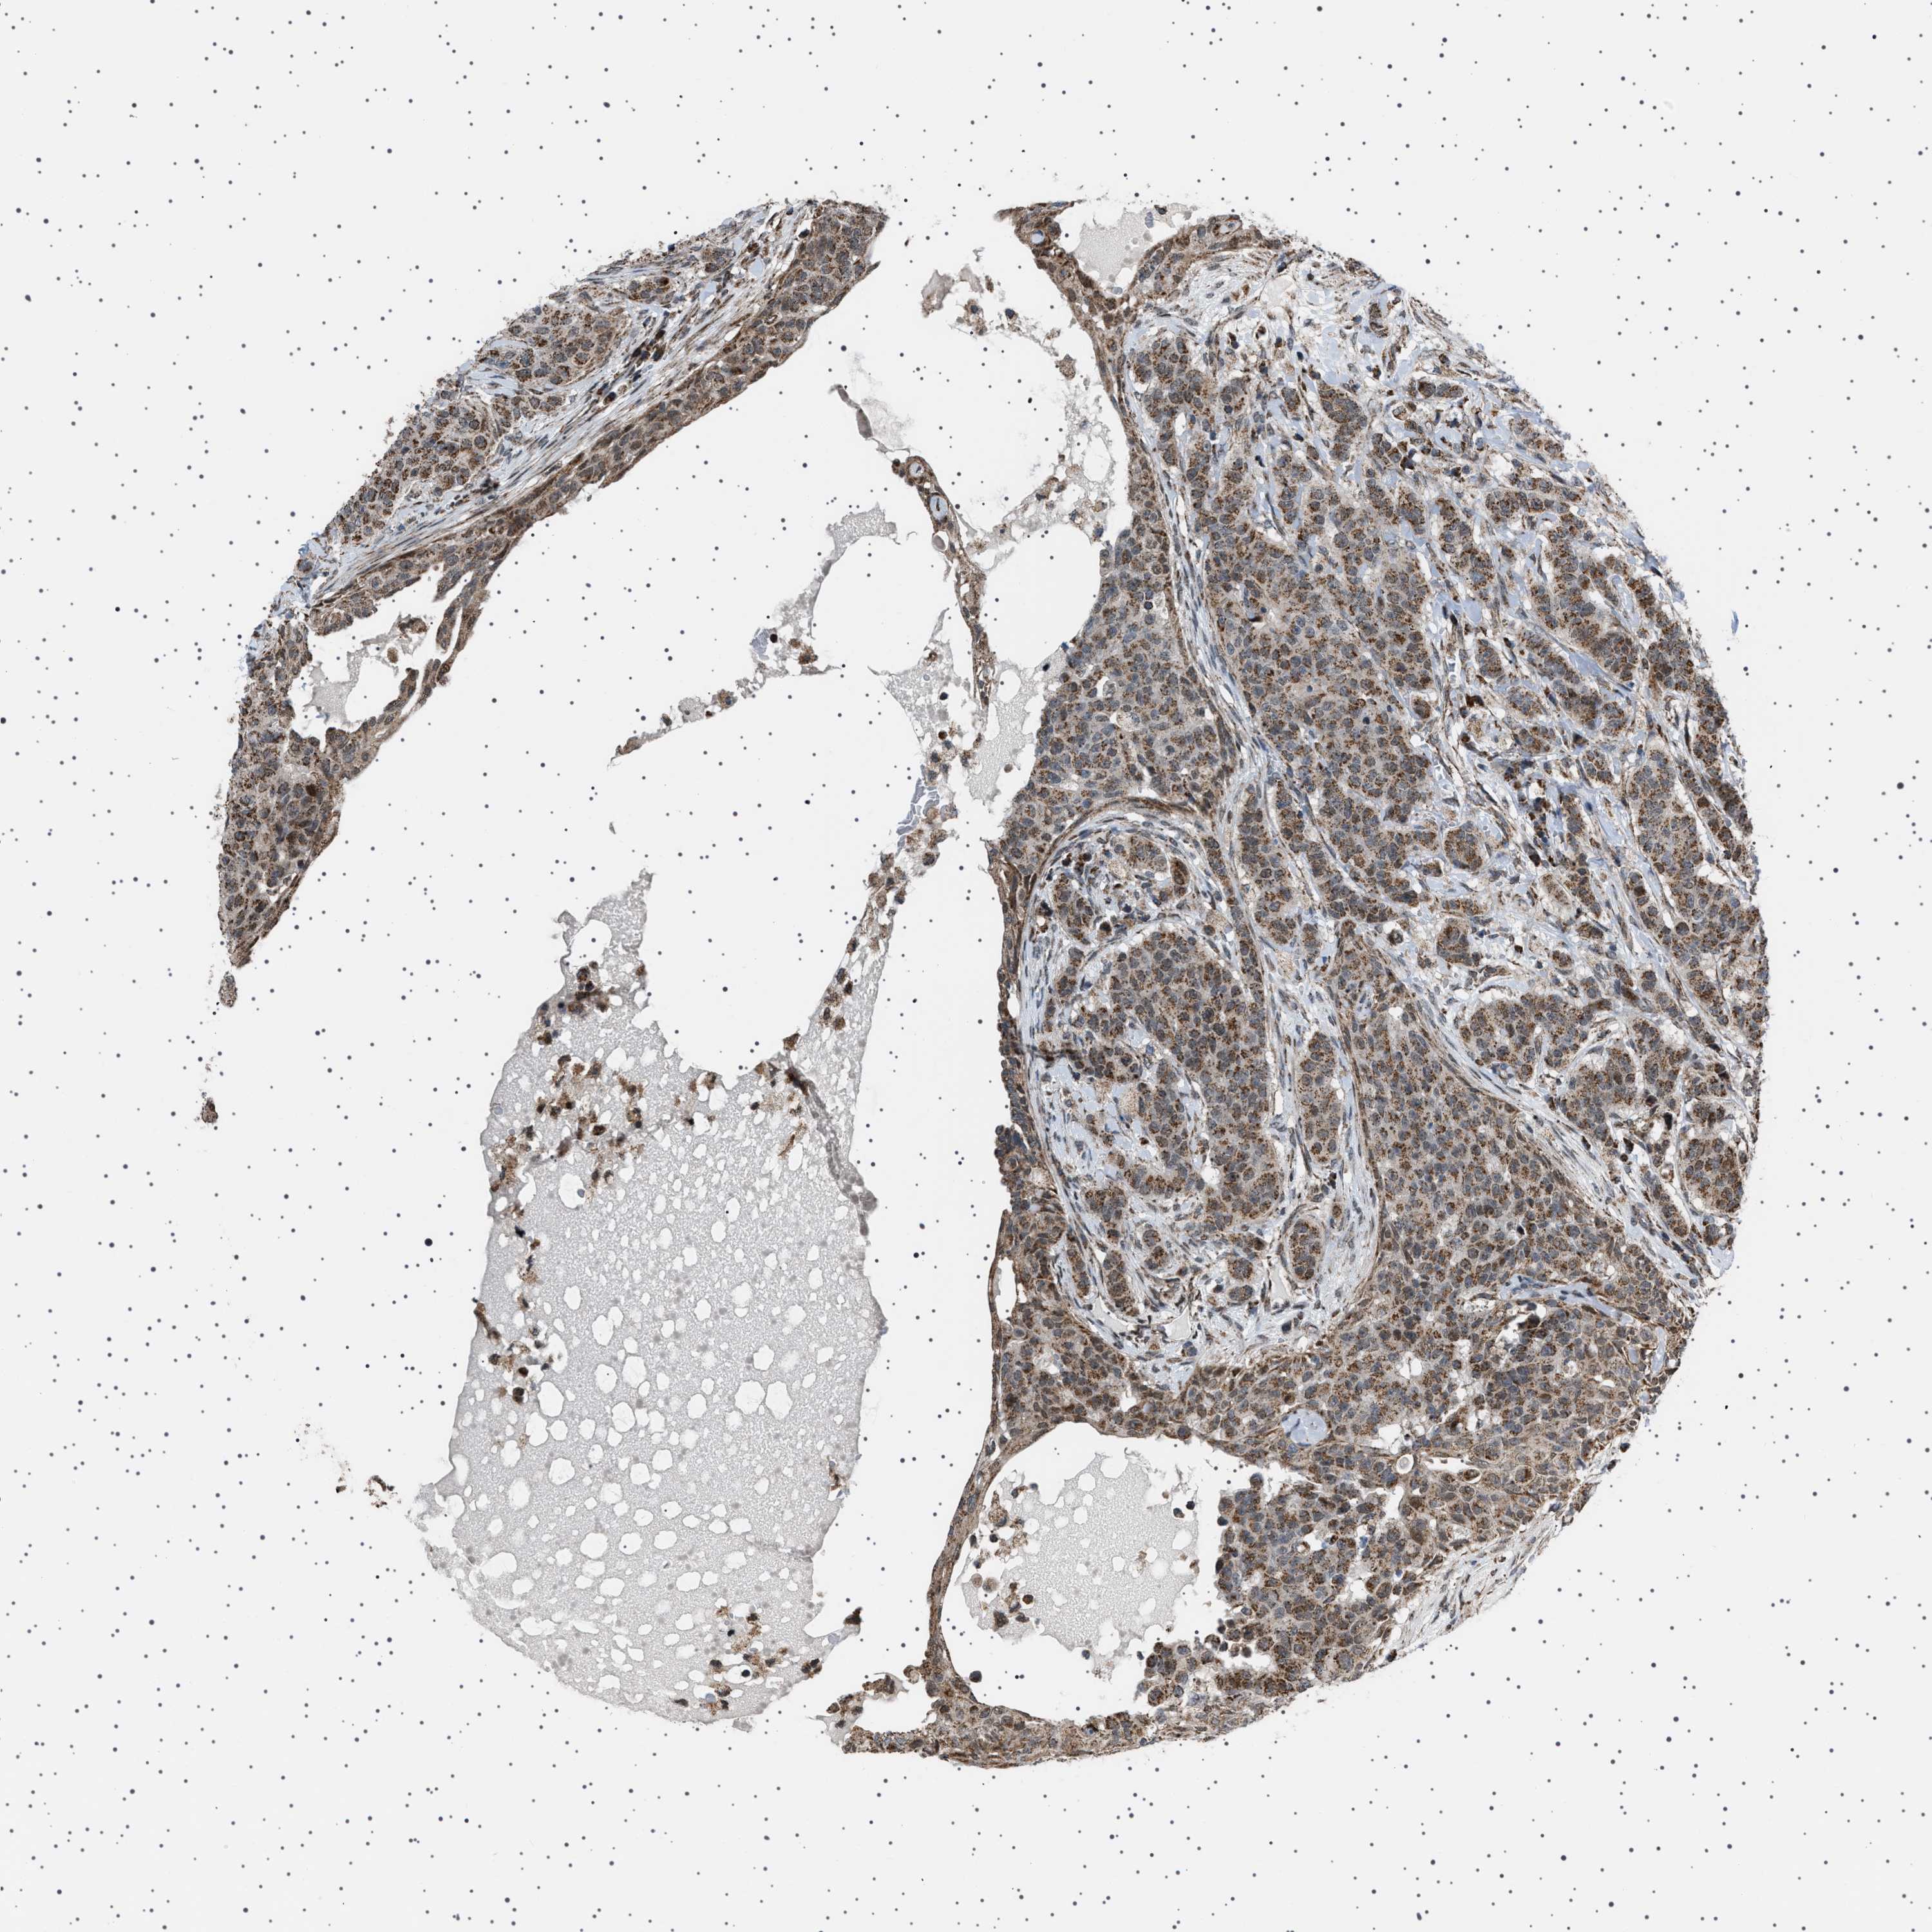

BRCA TCGA BRCA VALIDATION PROTEIN EXPRESSION

ANTIBODIES

AND

VALIDATION